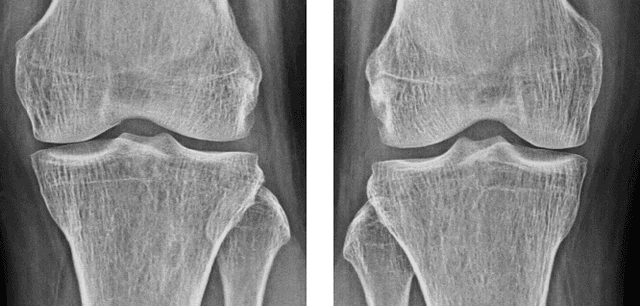

Abstract:The severity of knee osteoarthritis is graded using the 5-point Kellgren-Lawrence (KL) scale where healthy knees are assigned grade 0, and the subsequent grades 1-4 represent increasing severity of the affliction. Although several methods have been proposed in recent years to develop models that can automatically predict the KL grade from a given radiograph, most models have been developed and evaluated on datasets not sourced from India. These models fail to perform well on the radiographs of Indian patients. In this paper, we propose a novel method using convolutional neural networks to automatically grade knee radiographs on the KL scale. Our method works in two connected stages: in the first stage, an object detection model segments individual knees from the rest of the image; in the second stage, a regression model automatically grades each knee separately on the KL scale. We train our model using the publicly available Osteoarthritis Initiative (OAI) dataset and demonstrate that fine-tuning the model before evaluating it on a dataset from a private hospital significantly improves the mean absolute error from 1.09 (95% CI: 1.03-1.15) to 0.28 (95% CI: 0.25-0.32). Additionally, we compare classification and regression models built for the same task and demonstrate that regression outperforms classification.